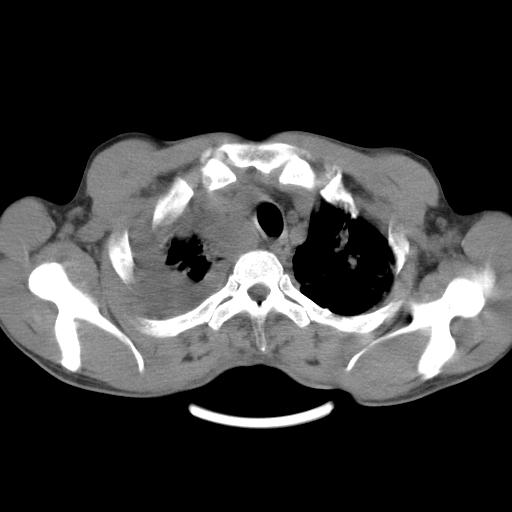

男性,44岁,结核病史多年。现胸闷气短,咳嗽,偶咳血。

右侧胸腔积液

右肺下叶不张

双肺多发结节影最分空洞形成考虑占位不除外结核

双肺陈旧性病变

1、右侧大量胸腔积液伴右肺压缩性膨胀不全,建议抽液治疗后复查 2、两肺继发性tb伴空洞形成。

1)两肺继发性肺结核伴空洞形成,左肺多发性结核球。2)右侧大量胸腔积液伴右肺部分膨胀不全。3)纵隔淋巴结肿大。